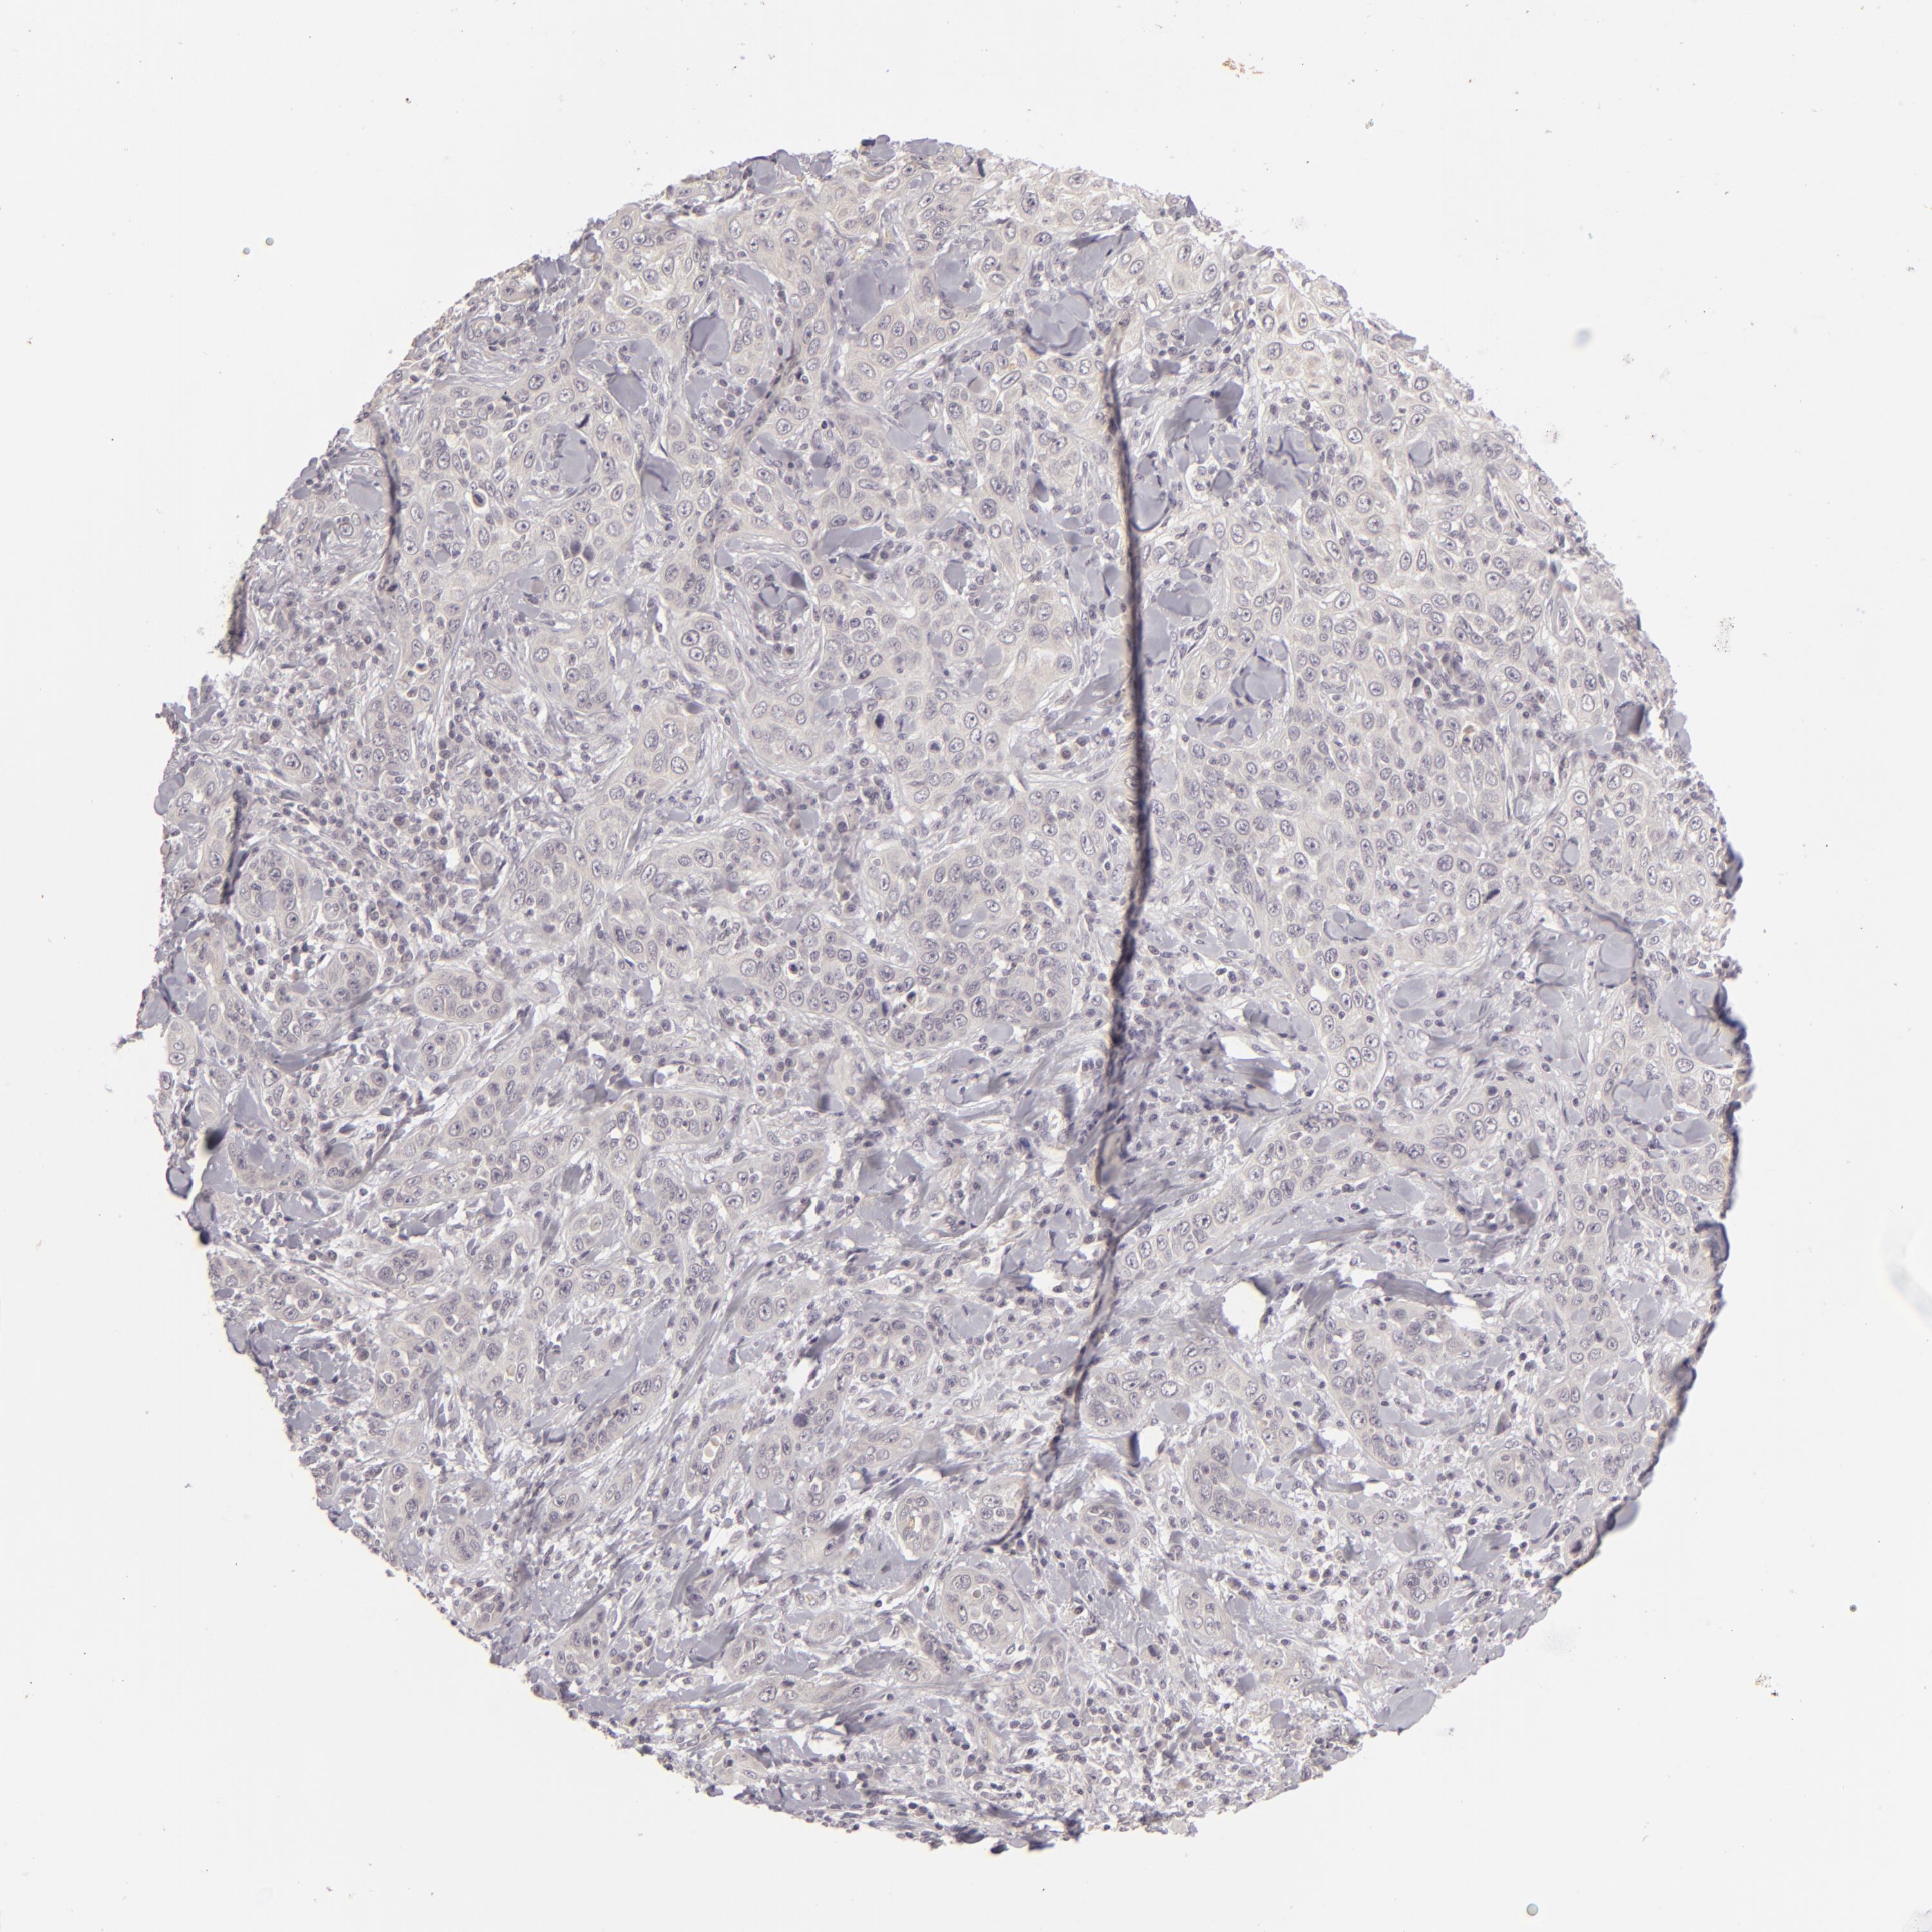

CANCER SKIN CANCER Show tissue menu

Basal cell and squamous cell cancer

SKIN CANCER - Protein expressioni

A mouse-over function shows sample information and annotation data. Click on an image to view it in a full screen mode. Samples can be filtered based on level of antibody staining by selecting one or several of the following categories: high, medium, low and not detected. The assay and annotation is described here.

Each image is clickable and will lead to virtual microscopy that enables deeper exploration of all samples and also displays staining intensity scores, fraction scores and subcellular localization as well as patient and tissue information for each sample.

Antibody HPA001733

Squamous cell carcinoma, NOS

Basal cell carcinoma